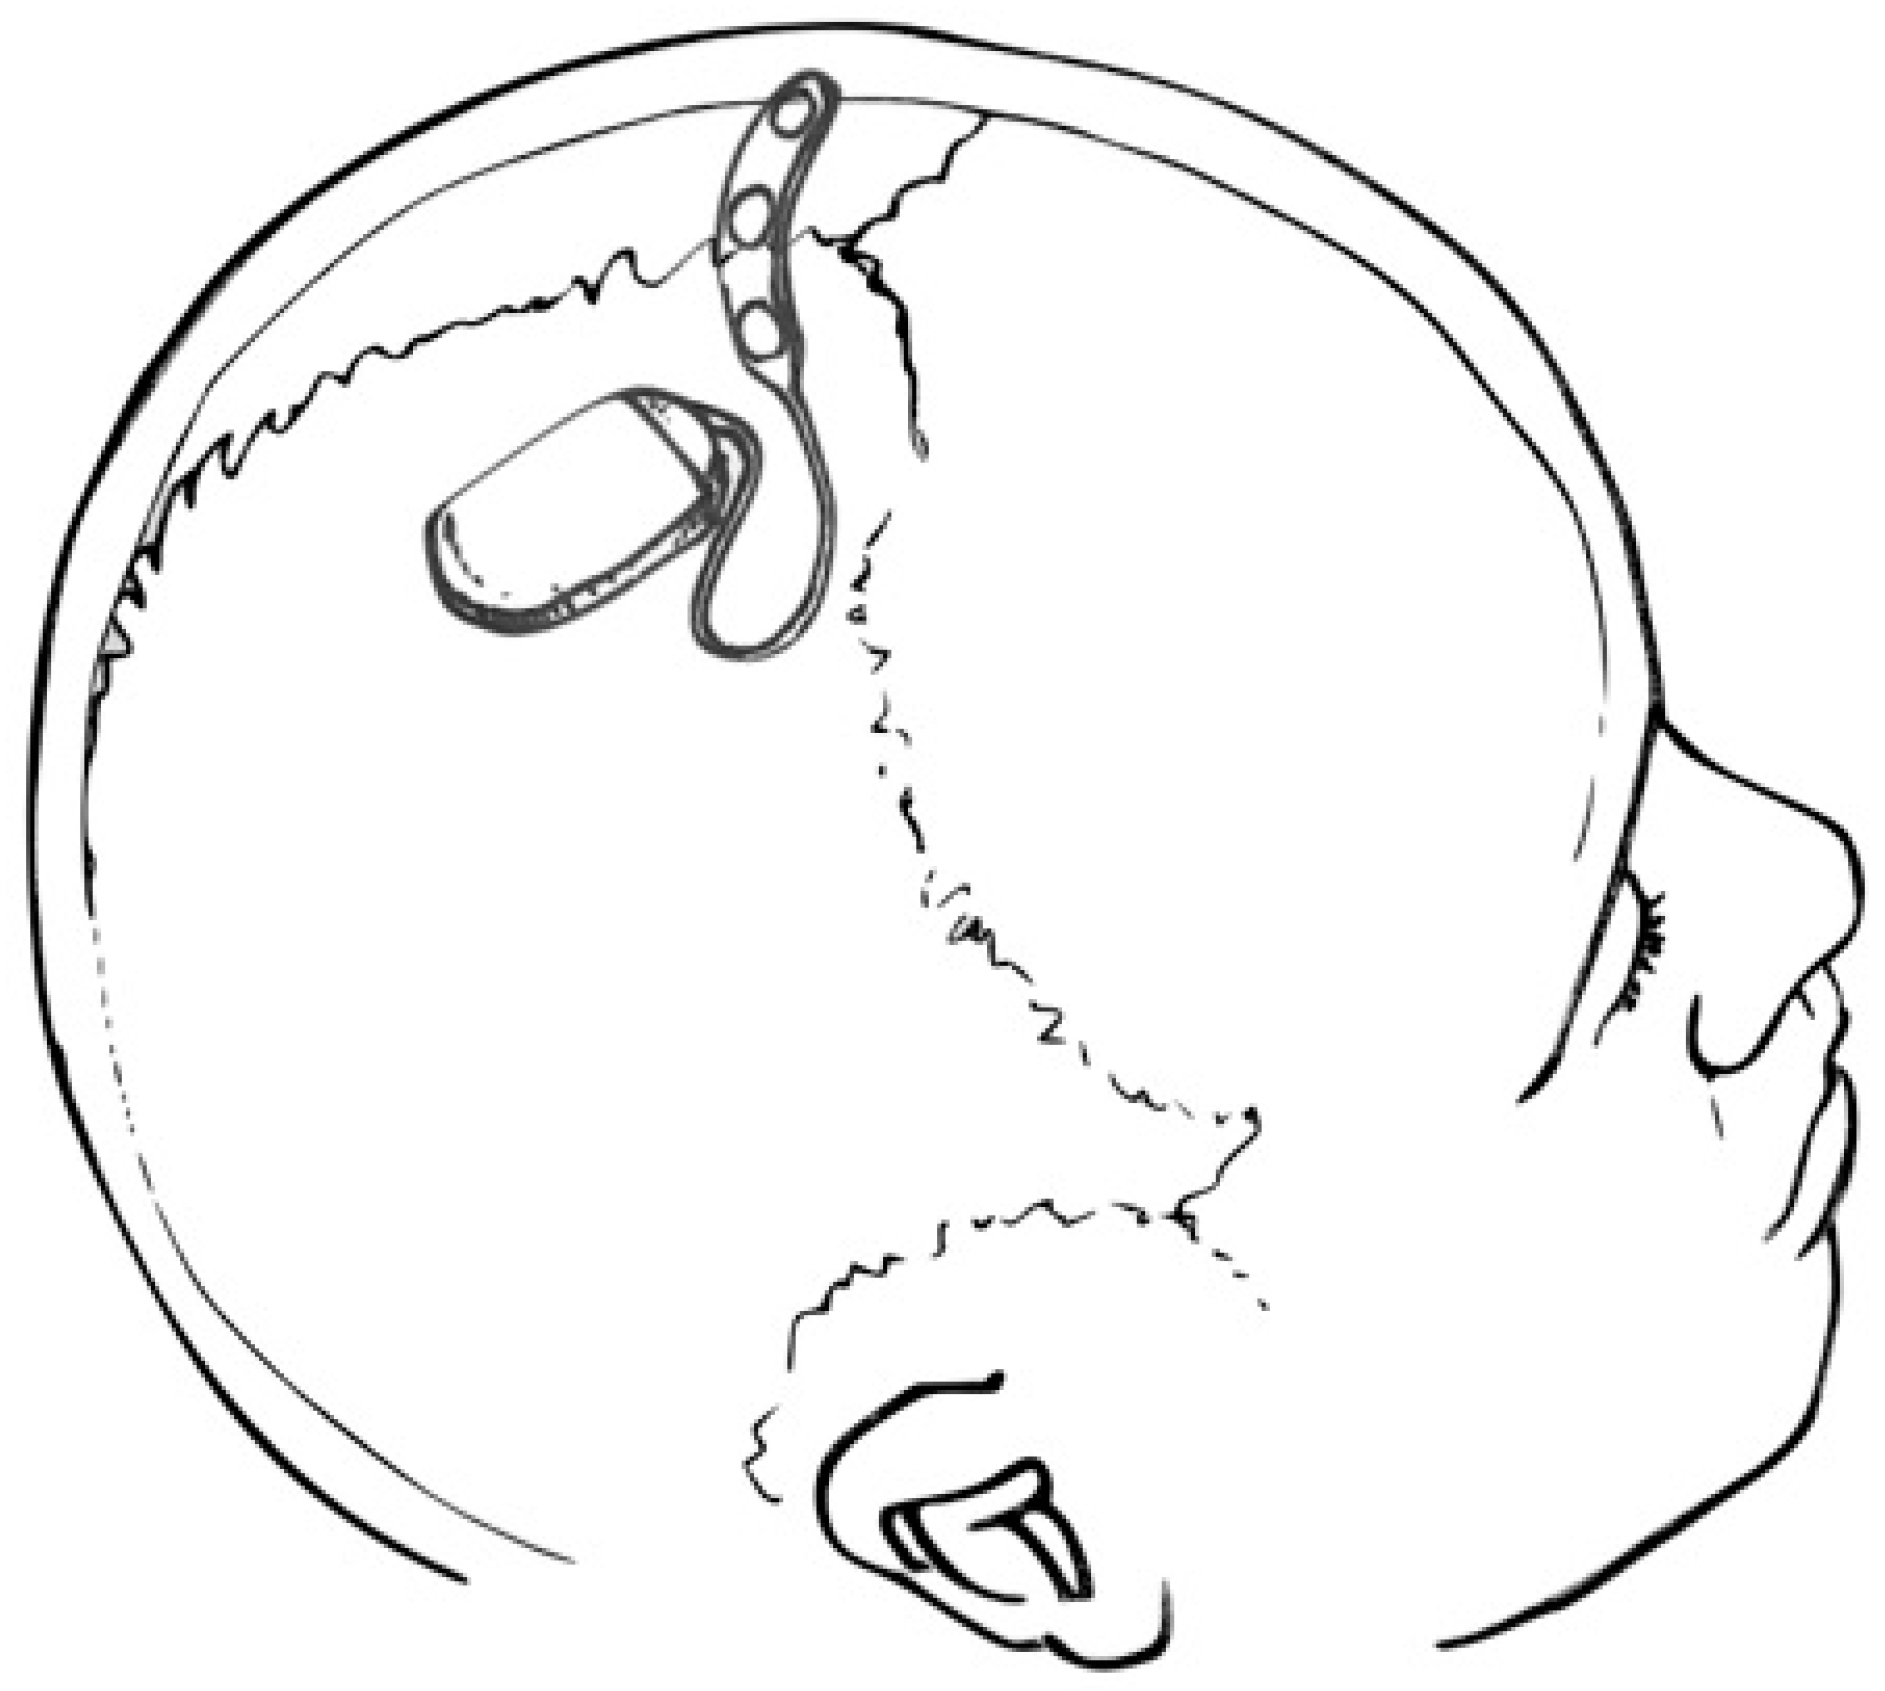

- Haneef, Z.; Yang, K.; Sheth, S.A.; Aloor, F.Z.; Aazhang, B.; Krishnan, V.; Karakas, C. Sub-scalp electroencephalography: A next-generation technique to study human neurophysiology. Clin. Neurophysiol. 2022, 141, 77–87. [Google Scholar] [CrossRef]